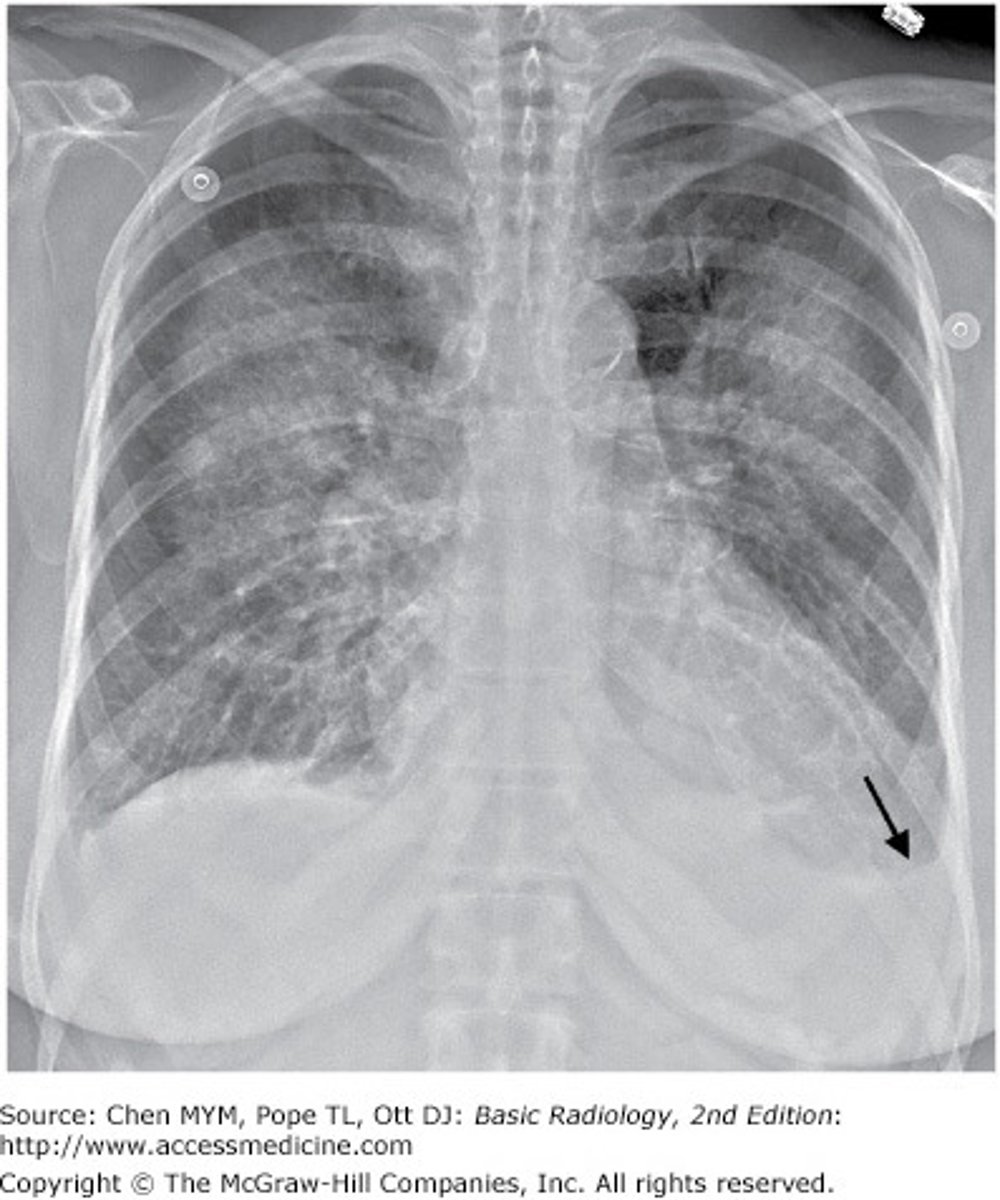

A 64 year-old woman with past medical history of hypertension presents to the clinic complaining of increasing cough and dyspnea over the past two weeks. Physical exam reveals dullness to percussion and decreased breath sounds at the bilateral bases. A chest x-ray is available below:

Which of the following is the most appropriate intervention for this patient?

The Correct Answer is: B

The patient has developed a pleural effusion most likely due to CHF based on the symptoms and presence of small bilateral pleural effusions. Initial interventions include diuresis and monitoring for resolution of symptoms and the effusion (B). If the effusion fails to improve or the patient develops dyspnea at rest then thoracentesis (E) is indicated. Additional therapy or intervention (A, C, E) should be considered if the patient's condition worsens and are informed by the results of thoracentesis.